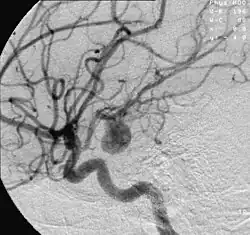

- Die Angiografie dient nicht nur dem Aneurysmanachweis, sondern wird zum Nachweis von Verschlusserkrankungen in peripheren oder zentralen Gefäßen wie etwa Nierenarterien begleitend eingesetzt.

Zerebrale Aneurysmen bzw. intrakranielle Aneurysmen treten an Hirnarterien auf. Die normalisierte Krankheitshäufigkeit (Prävalenz) ist drei Prozent. Zerebrale Aneurysmen treten verstärkt bei Menschen ab dem 40. Lebensjahr auf. Frauen sind im Verhältnis 5:3 häufiger betroffen als Männer.[8]

Die zentrale Gefahr eines Gehirnarterienaneurysmas ist die Ruptur, also ein Platzen, welches einen schädlichen Blutaustritt in den Gehirnraum zur Folge hat. Eine solche Subarachnoidalblutung verursacht einen Schlaganfall (Apoplex), betrifft sechs bis neun Personen pro 100.000 Personen pro Jahr und endet in 35 Prozent der Fälle tödlich. Viele Patienten erleiden bleibende Behinderungen, die oft mit kognitiven Einschränkungen einhergehen.[9]

Die drei wichtigsten Therapien zur Behandlung zerebraler Aneurysmen, die abhängig von ihrer Lokalisation, Form und Größe eingesetzt werden, werden im Folgenden kurz erläutert.

- Bei der konservativen Therapie wird kein Eingriff vorgenommen, sondern das Aneurysma wird durch regelmäßige Kontrolle mittels bildgebender Verfahren (normalerweise Angiografien) beobachtet. Besonders bei kleinen nicht-symptomatischen Aneurysmen ist dies aufgrund des geringen Rupturrisikos eine Option.

- Bei der endovaskulären Therapie werden mittels eines hohlen Mikrokatheters über die Leistenarterie sogenannte Coils (Spiralen aus einer Platinlegierung) in den Aneurysmasack gebracht. Diese Coils füllen das Aneurysma zwar nur zu etwa 10 % bis 30 % aus, verursachen aber eine Thrombenbildung und verhindern so die weitere Blutzirkulation im Aneurysma und somit eine Ruptur. Ein Vorteil des Eingriffes ist, dass keine offene Operation am Gehirn durchgeführt werden muss.

- Bei der neurochirurgischen Therapie wird das Aneurysma über eine Kraniotomie (offene Hirn-Operation) behandelt. Der Aneurysmasack wird mittels eines Clips abgeklemmt. Somit ist das Aneurysma vom Blutkreislauf ausgeschlossen. Alternativ können auch Stents eingesetzt werden, um die Arterienwand zu verstärken oder die Flusseigenschaften zu verändern und so eine Thrombosierung zu fördern.